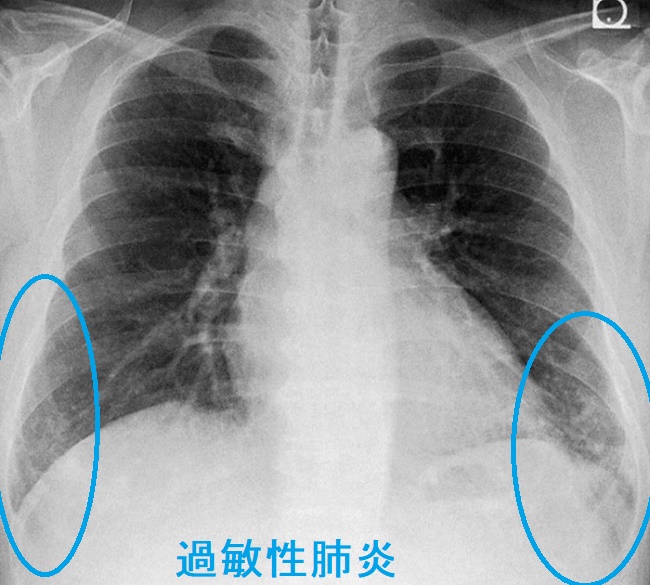

過敏性肺炎 胸部エックス線写真

両側下肺野にスリガラス影

過敏性肺炎 CT画像

両側肺野に小葉中心性粒状影